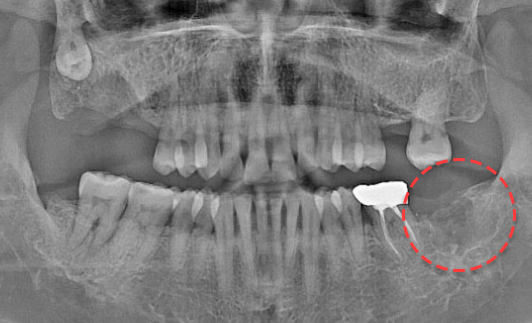

왼쪽 하악 매복 사랑니 발치 Before X-Ray

치료시작일

2020.05.24

AFTER

왼쪽 하악 매복 사랑니 발치 After X-Ray

치료종료일

2020.06.29

왼쪽 하악 매복 사랑니 발치